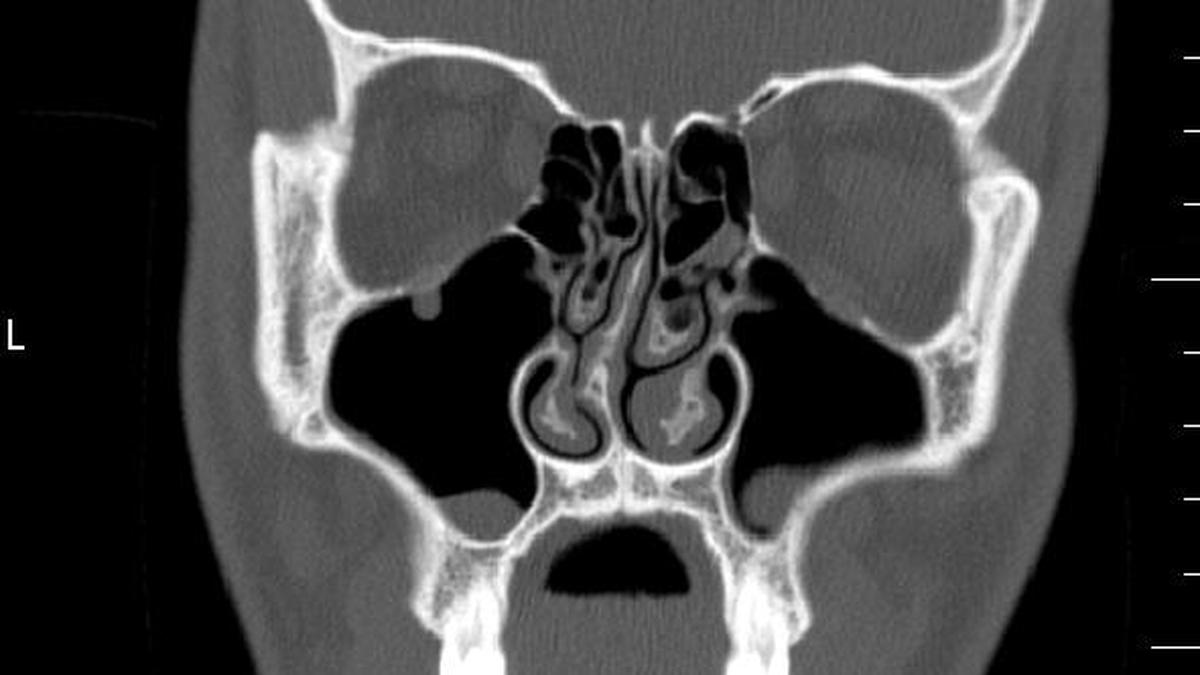

For diagnosis, clinical examination remains the standard. “We can diagnose a bend just by examination and further confirm it with either an endoscopic examination or CT scan,” says Shruthi Sreekumar, associate consultant, ENT, Rela Hospital, Chennai. In some cases, a CT scan of the paranasal sinuses helps clarify associated disease.